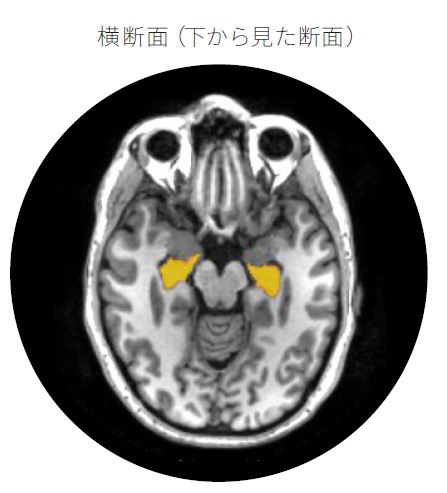

海馬はどこにあり、どのくらいの大きさですか?

海馬は大脳側頭葉の内側部にあり、タツノオトシゴのような形をしています。左右に一対ずつあり、それぞれ小指ほどの大きさです。